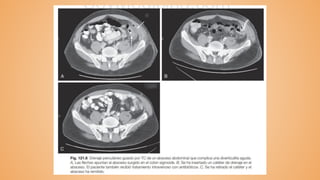

● Perforación u obstrucción ---> TAC con doble contraste

------------- DIVERTICULITIS ------------- Inflamacióno infección relacionadas con divertículos, o ambas. ● Complicación más frecuente ● Aparece en un 10-25% de los casos El cuello del saco ventricular se obstruye por heceses pesadas; el fecalito erosiona la mucosa del saco, produce una inflamación de bajo grado y obstruye su drenaje Diagnóstico: ● Dolor abdominal ---> radiografía simple de abdomen ● Perforación u obstrucción ---> TAC con doble contraste ● Endoscopia ✘